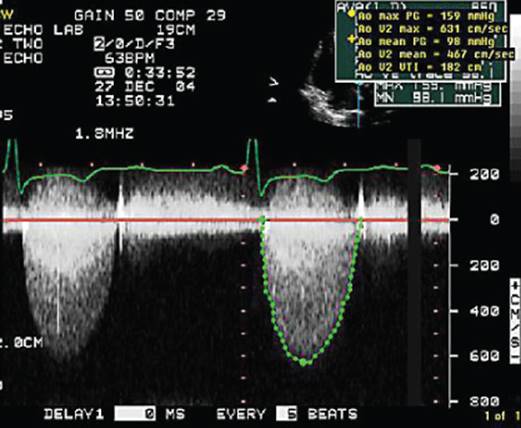

The high-pitched sound waves are sent through a transducer and the device picks up the echoes as they bounce off the tissue of your heart. The echoes are converted into moving images of the heart, which can be viewed on a video screen. There are different types of echocardiograms, which include:

What is the test that determines how blood flows through the heart?

This test is usually performed to find out if there is a decrease in blood flow to the heart, which usually occurs in coronary artery disease. Doppler echocardiogram, which determines how your blood flows through your heart’s chambers, valves, and blood vessels.